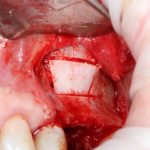

Глянем на то, что получилось:

Осталось адаптировать костный блок (убрать острые края), проверить его фиксацию и, при необходимости, добавить винты. Десятисекундное дело.

Изоляция области аутографта и имплантатов барьерной мембраной.

Перекрывать костный блок барьерной мембраной или оставить так? По этому вопросу есть много мнений. Между тем, в публикации по методике есть ясное показание, когда это требуется.

Конкретно в этом клиническом случае между костным аутотрансплантатом, ложем и имплантатами есть пустое пространство. Если его не изолировать от мягких тканей, они прорастут и осложнят интеграцию аутографта. Поэтому я решил перекрыть костный блок барьерной мембраной, пусть это делает хирургическую операцию немного дороже.